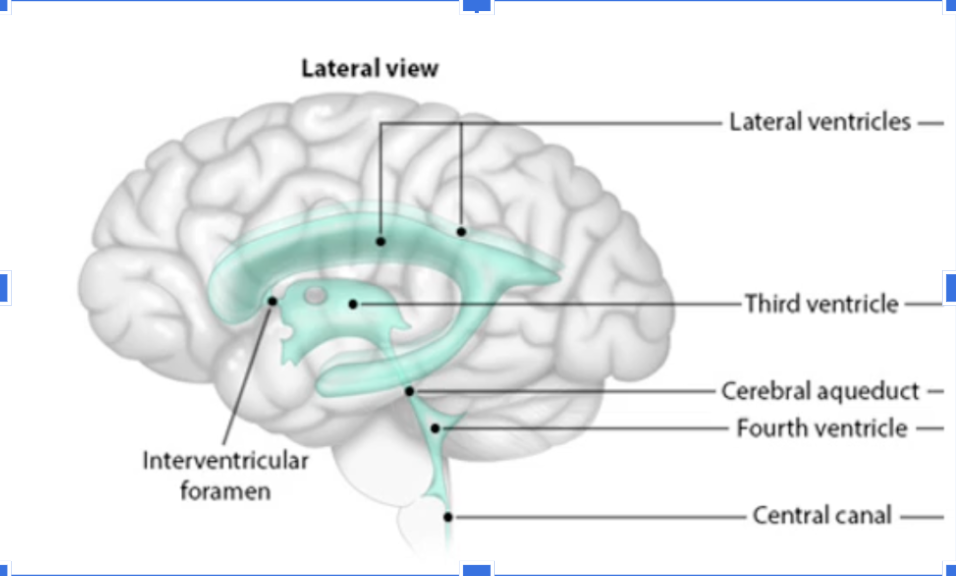

Trace CSF flow from Ventricles to Fourth Ventricle

Lateral Ventricles —> interventricular foramen—>Third Ventricle—> Cerebral aqueduct—>fourth ventricle

After leaving the Fourth Ventricle, where does the CSF go

It flows to the central canal or around the subarachnoid space to leave the brain